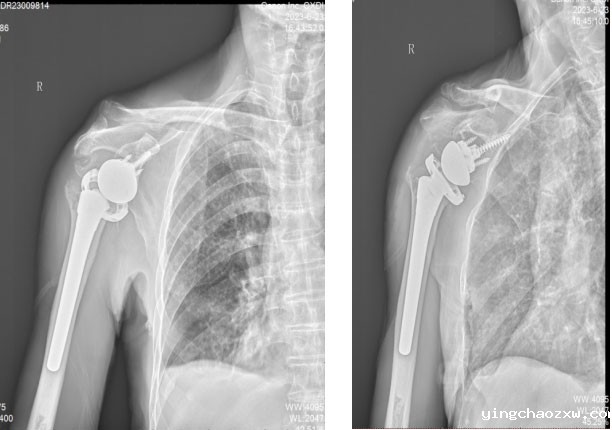

5.术后X片。

据悉,该患者为男性,现年85岁,近年来反复感觉右侧肩关节疼痛不适,屡次开展保守治疗,但效果不佳。近半月来疼痛加剧,肩关节活动障碍,严重困扰患者日常生活。患者入院后,陈志强主任医师及其团队认真研讨患者病情,因患者肩袖多年陈旧性断裂已经无法修复,传统全肩关节置换术治疗此类病例肩关节功能根本不能改善和恢复,团队最终决定为患者选择了目前业界治疗此类疾病的最佳治疗方案——反置式肩关节置换术进行治疗。在陈志强主任医师和骨外科全体医务人员的共同努力下,本次手术非常顺利,历时1小时即告完成。术后一周,患者肩关节疼痛消除,功能恢复良好,患者及家属对治疗效果非常满意。